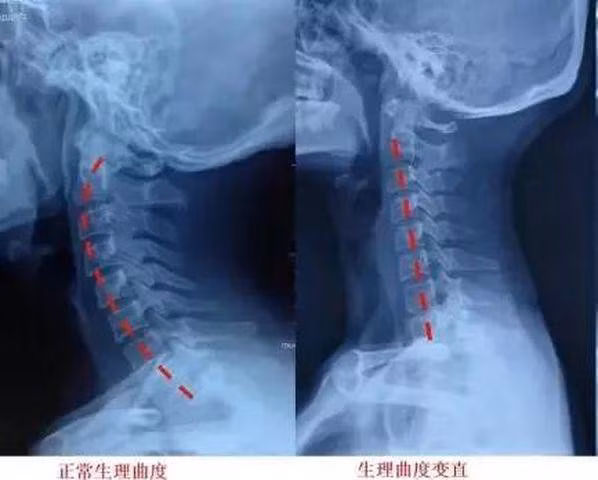

Ảnh chụp X quang cho thấy cột sống cổ của Tiểu Dương chuyển thành đường thẳng đứng và mất đi độ cong sinh học

Cột sống cổ của cơ thể con người, thực tế không phải là hoàn toàn thẳng đứng, mà có một đường cong tự nhiên. Đường cong này có thể khiến xương cổ tránh được tổn thương do những ngoại lực bên ngoài tác động lên cổ. Nhưng cúi đầu trong thời gian dài, khiến xương cổ phải chịu áp lực rất lớn, đều sẽ khiến cho cột sống cổ bị biến đổi thành đường thẳng đứng. Điều này thực tế còn là một loại chấn thương đối với cột sống cổ.